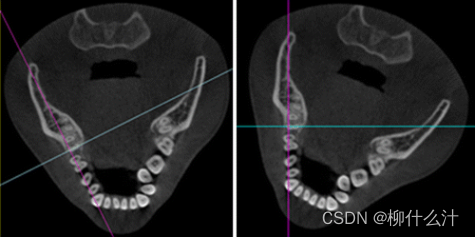

改造可以沿着手动或自动绘制的曲线进行。最常见的是沿牙弓绘制全景曲线,以生成一系列牙齿和骨骼的合成全景图(图00和01)。由于这些合成全景图像的厚度较小,通常不可能在一张图像中看到上下牙弓的情况。因此,通常需要为上、下牙弓分别绘制曲线(图02)。另外,可以计算出这些合成全景图的射线和,类似于从全景X光片上获得的图像。图23显示了不同厚度的合成全景堆叠的射线和全景图像。

上颚(顶部)和下颚(底部)的合成全景图像。